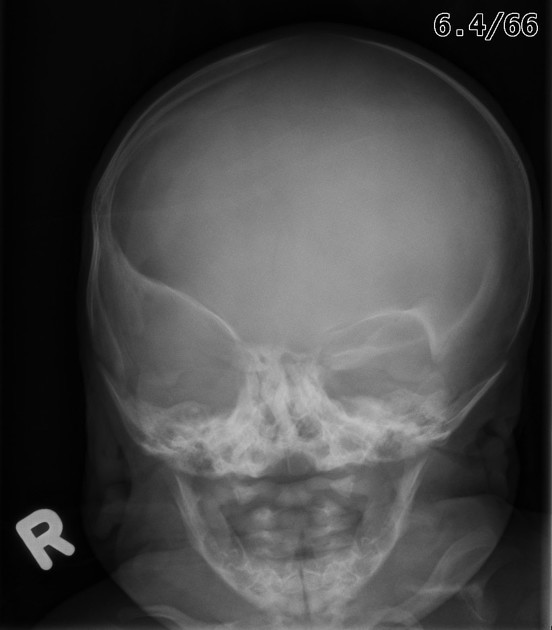

Copper beaten skull

A

Primary:

Raised intracranial pressure in children.

Other:

Craniosynostosis

Obstructive hydrocephalus

Hypophosphatasia

Intracranial masses